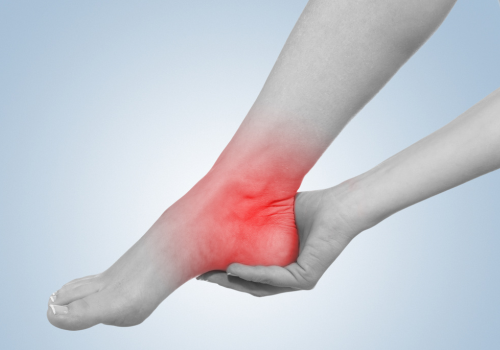

捻挫

「捻挫」とは、関節をひねった際に、靭帯など周辺の組織が引き伸ばされたり、切れてしまう状態のことです。今回は、足の関節に絞って、捻挫について詳しく解説していきます。

足首の捻挫は、スポーツ外傷の中で最も多く、旭市の旭こうご接骨院・整体院でも頻繁に診る症状の一つです。 急に止まった時など、ほとんどの場合、足の関節を内側にひねってしまい、捻挫を引き起こします(内反捻挫)。

捻挫とは、関節をひねり、靭帯など関節周辺の組織を損傷することです。 捻挫を起こすと、痛み、腫れ、熱感などの炎症症状が現れます。